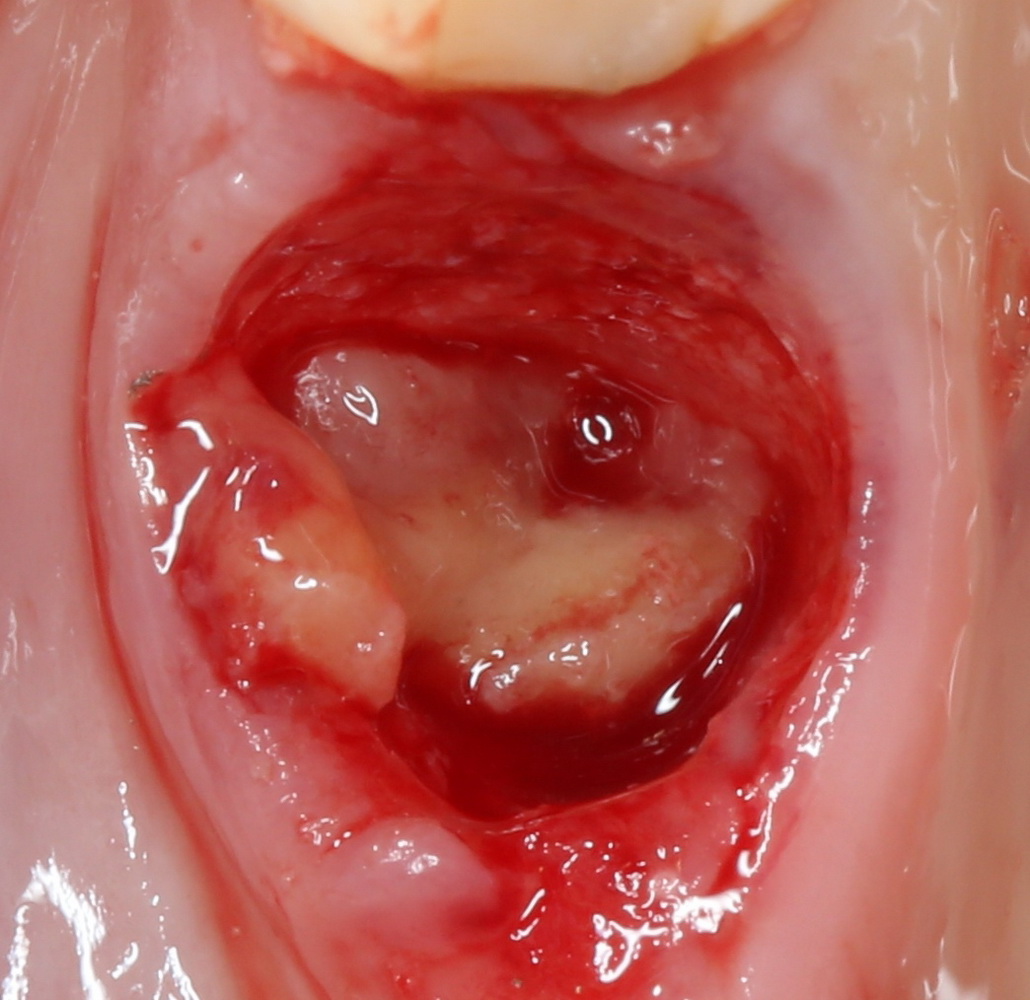

Клиническая картина в области удаленного зуба через полтора месяца:

Мечта имплантолога, не правда ли? Это я к тому, что не нужно ждать по полгода после удаления зуба — такой длительный срок ожидания приводит к сильной потере костной ткани. Не нужно превращаться в китайского пионера — самому себе создавать сложности, а потом героически их преодолевать.

Делаем разрез, скелетируем костную ткань. Вот еще один сюрприз:

Лунка зуба полностью регенерировала! Состояние костной ткани превосходное!

Это еще раз подтверждается, когда мы готовим лунку под имплантат: